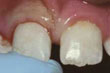

Et stort stykke av en fortann er slått av

En tann hvor et lite stykke er brukket av - Hvis du ikke har vondt og det manglende stykke er lite, haster det ikke med å oppsøke tannlege. I mange tilfeller kan den oppståtte ujevnheten fjernes med en lett avpussning. Er skaden litt større og kosmetisk uheldig kan den repareres med en plastfylling. La tannlegen vurdere optimal behandling. Hvis det manglende stykke stammer fra en fylling, vil ofte hele fyllingen legges om/revideres.